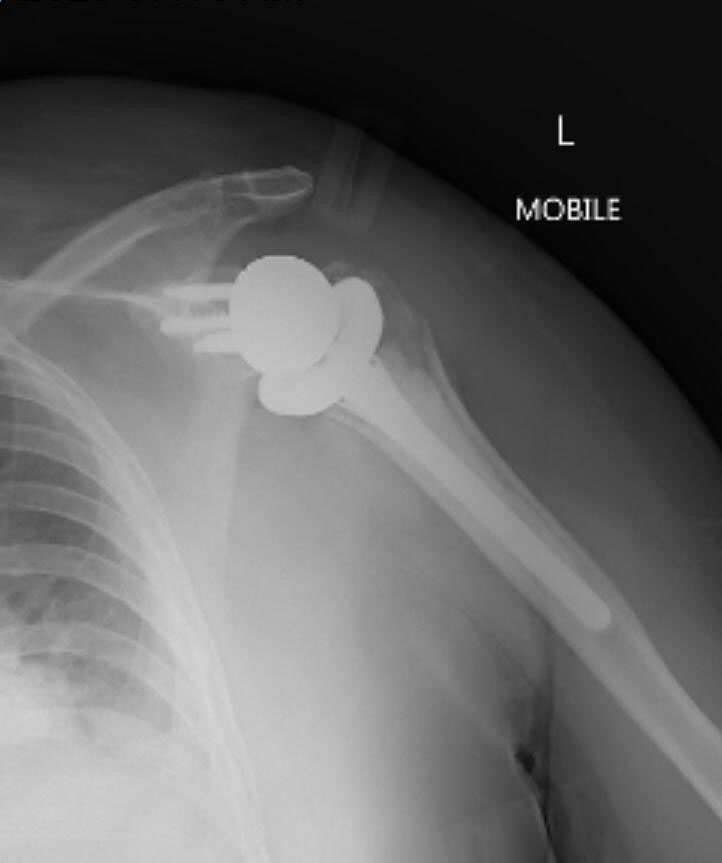

This 76 year-old female suffered a significant fracture of her humerus after tripping and falling up a stair.

This 76 year-old female suffered a significant fracture of her humerus (the bone of the upper arm) after tripping and falling up a stair. The head of the humerus, which forms the ball of the shoulder joint, was broken entirely off the shaft of the bone and had dislocated out of its normal position. The shaft of the humerus had shattered into several pieces and migrated up towards the shoulder.

After looking at the images and discussing her options, the patient chose to undergo surgical management. When fractures are as extensive as this one, it is often preferable to replace the shoulder joint entirely. In this case a reverse shoulder replacement was performed, which switches the position of the ball and socket in the joint to compensate for damage to the surrounding rotator cuff muscles.